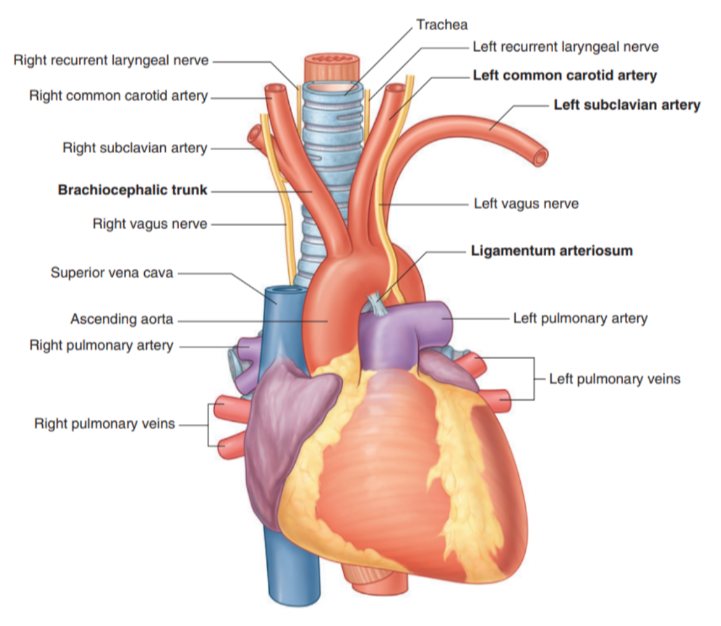

Arch of aorta

The thoracic portion of the aorta can be divided into the ascending aorta, arch of the aorta, & thoracic (descending) aorta —

Only the arch of the aorta is in the superior mediastinum

The arch extends as high as the midlevel of the sternal manubrium & is initially anterior, but later moves laterally to the trachea

From the arch we have 3 branches, each of which is crossed by the left brachiocephalic vein —

Brachiocephalic trunk

Left common carotid artery

Left subclavian artery

In this region we can also recognize the ligamentum arteriosus which is formed from the embryological structure known as the ductus arteriosus.

Branches of arch of aorta

Brachiocephalic trunk —

Largest of the three branches

Originates from behind the manubrium — slightly more anterior than the other branches

At the upper edge of the right sternoclavicular joint divides into —

Right common carotid — supplies right side of head

Right subclavian artery — supplies right upper limb

In some cases may have another branch for the supply of the thymus

Thyroid Ima Artery

Left common carotid artery:

Arises from the arch immediately to the left and slightly posterior to the brachiocephalic trunk

Ascends through the superior mediastinum along the left side of the trachea

Supplies the left side of the head and neck.

Left subclavian artery:

Arises from the arch of the aorta immediately to the left of, and slightly posterior to the left common carotid artery

Ascends through the superior mediastinum along the left side of the trachea

The major blood supply to the left upper limb.